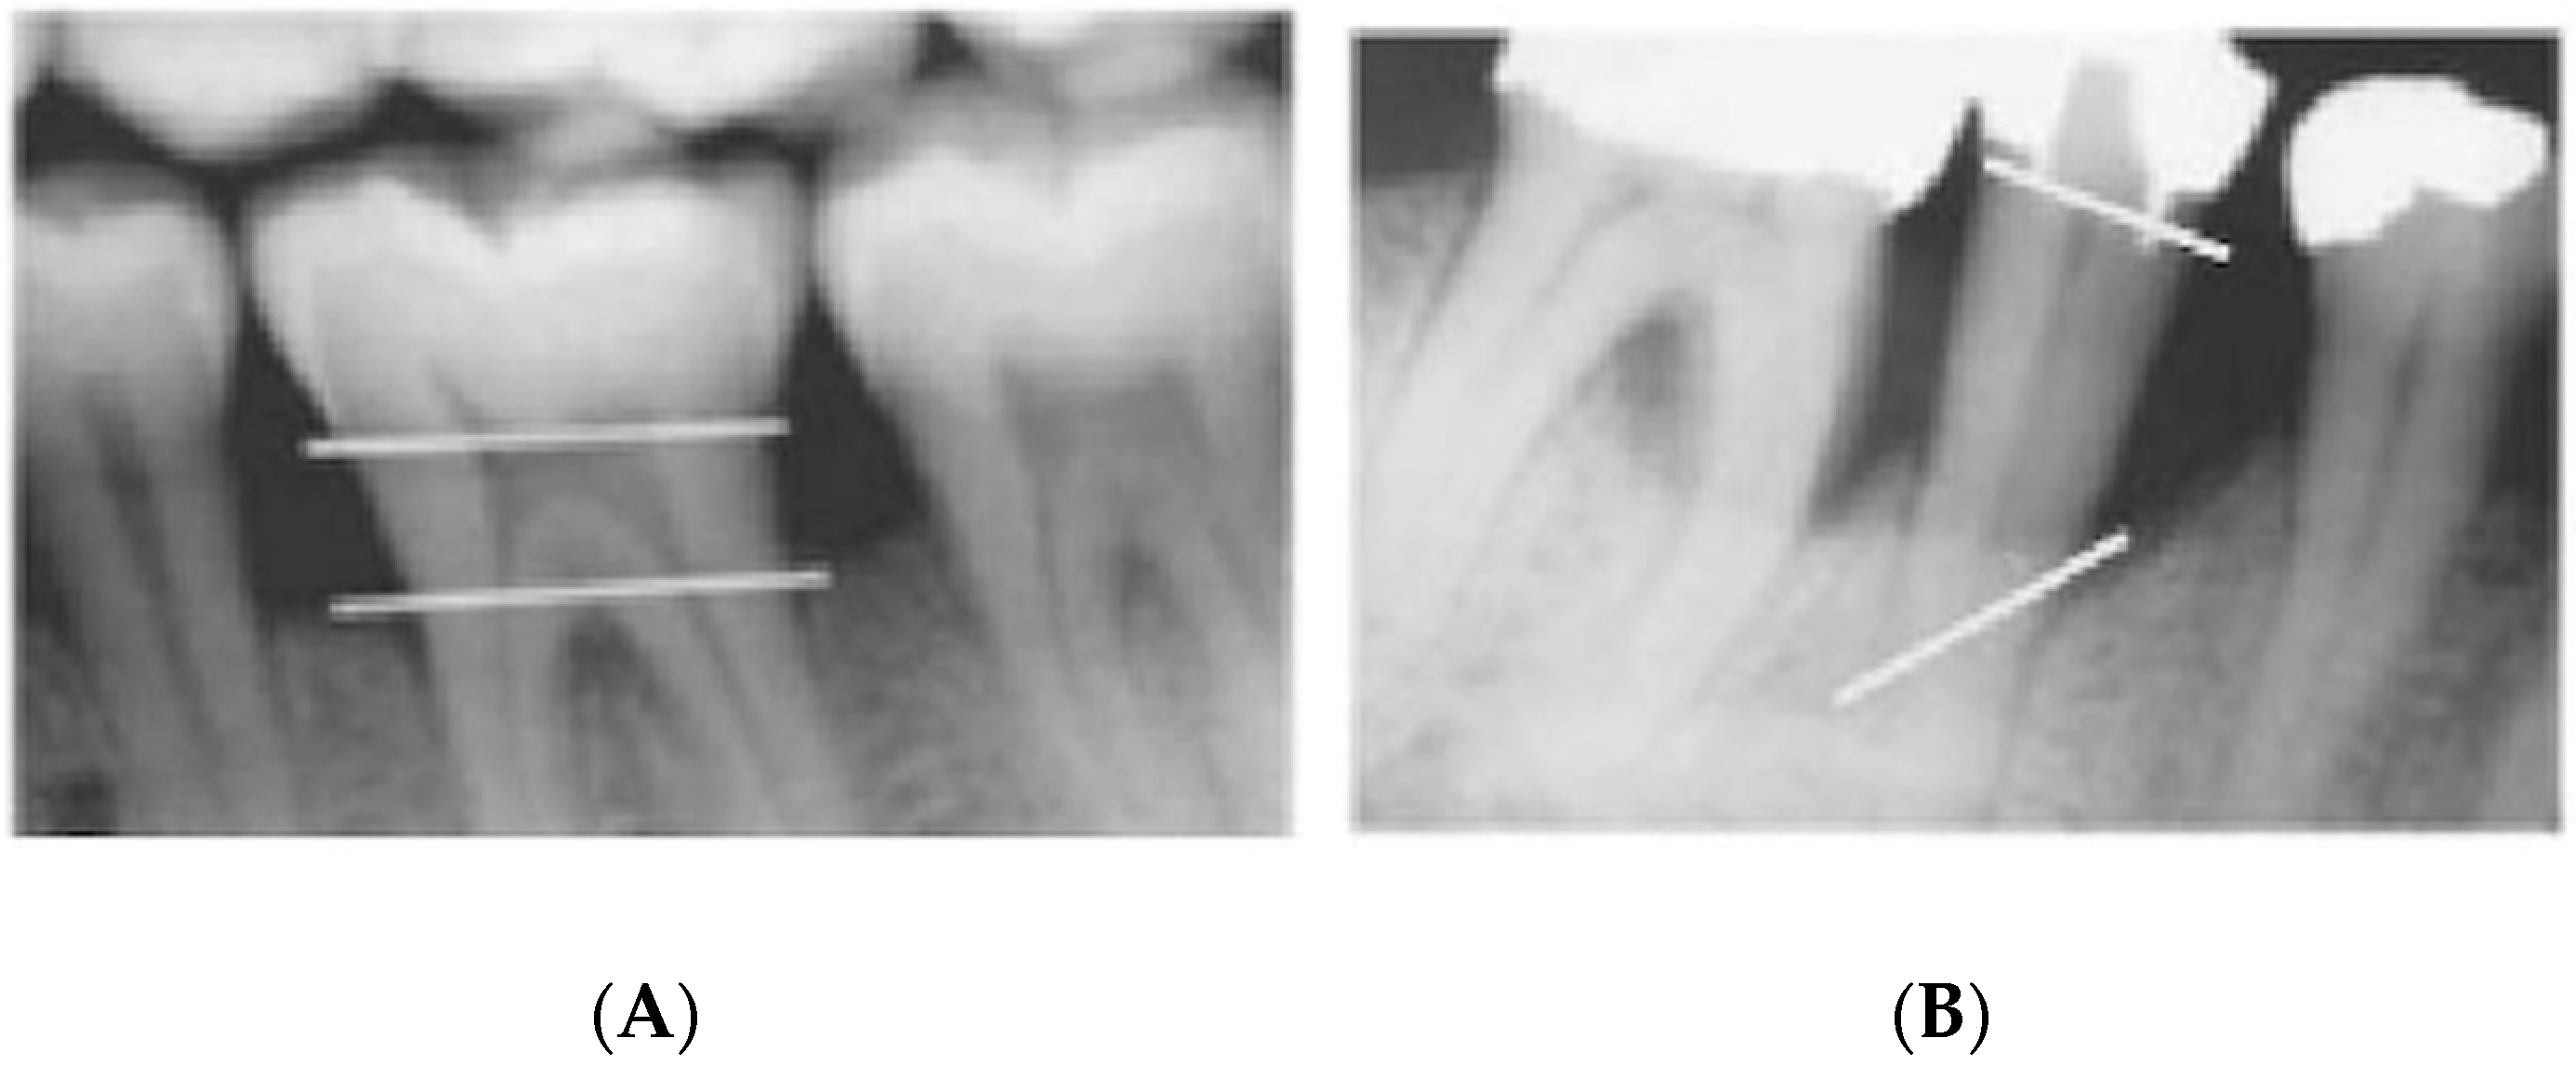

The proposed visual and radiographic interpretation techniques to determine the severity and pattern of iABL are illustrated in Figure 2 and Figure 3.

Figure 3.

Radiographic interpretation in terms of periodontal bone loss pattern which is classified into (A) horizontal bone loss and (B) vertical bone loss.